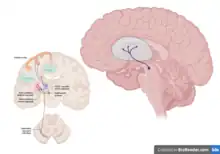

| Tuberoinfundibular pathway | The tuberoinfundibular pathway transmits dopamine from the hypothalamus to the pituitary gland.

This pathway controls the secretion of certain hormones, including prolactin, from the pituitary gland.[9] "Infundibular" in the word "tuberoinfundibular" refers to the cup or infundibulum, out of which the pituitary gland develops. |

Tuberoinfundibular pathway

The tuberoinfundibular pathway transmits dopamine the hypothalamus to the pituitary gland. This pathway also regulates the secretion of prolactin from the pituitary gland, which is responsible for breast milk production in females. Hyperprolactinemia is an associated condition caused by an excessive amount of prolactin production that is common in pregnant women.[29]

- ↑ Malenka RC, Nestler EJ, Hyman SE (2009). "Chapter 10: Neural and Neuroendocrine Control of the Internal Milieu". In Sydor A, Brown RY (eds.). Molecular Neuropharmacology: A Foundation for Clinical Neuroscience (2nd ed.). New York: McGraw-Hill Medical. p. 249. ISBN 9780071481274.

Relationship of the hypothalamus and the pituitary gland. The anterior pituitary, or adenohypophysis, receives rich blood flow from the capillaries of the portal hypophyseal system. This system delivers factors released by hypothalamic neurons into portal capillaries at the median eminence. The figure shows one such projection, from the tuberal (arcuate) nuclei via the tuberoinfundibular tract to the median eminence.